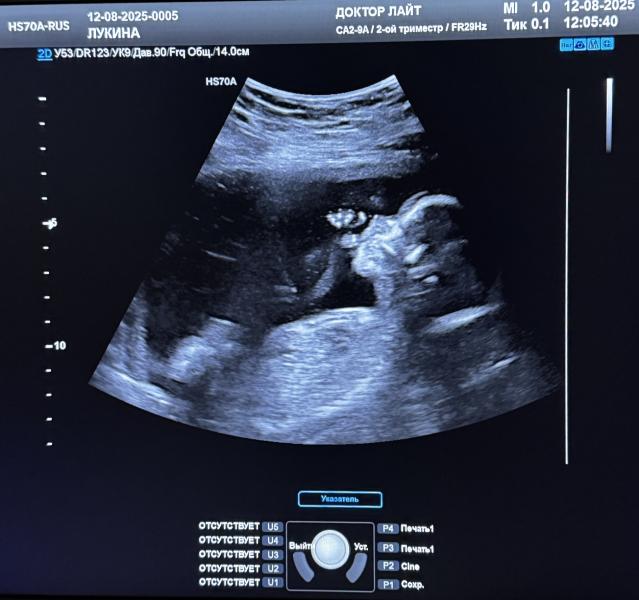

Узнали пол малышки на УЗИ: наша радость!

Ходили с мужем на узи, узнали пол😍

Наша малышка 🩷